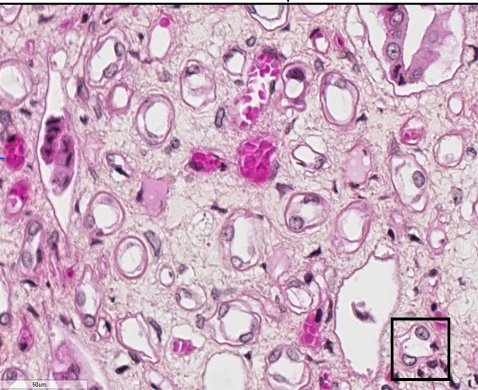

L’image représente quelle type de cellule ( lame vessie )

Épithélium de transition

Q

Comment on appelle l’épithélium de l’image ( vessie )

Dans l’image les épaississement du pole apicale représente quoi

Les plaques membranaires qui sont une spécialisation du pôle apical de l’épithélium urinaire